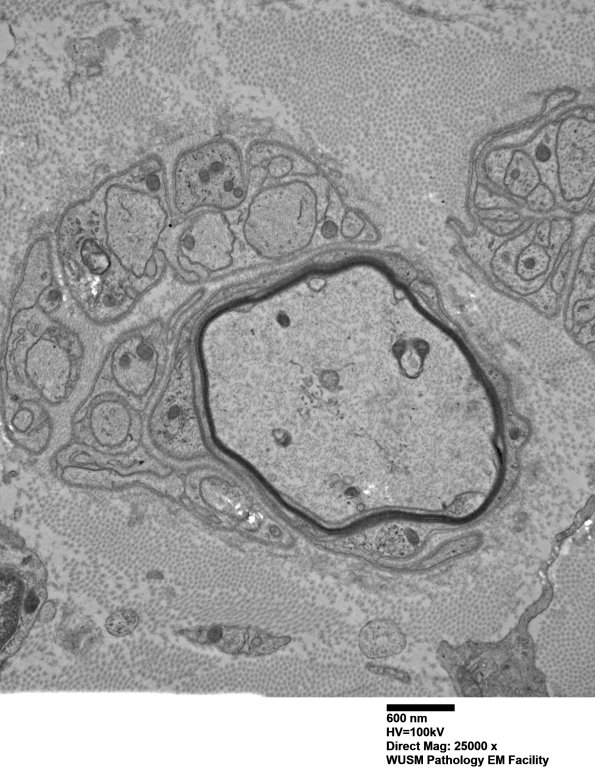

Large axons with remyelination. (electron micrograph)